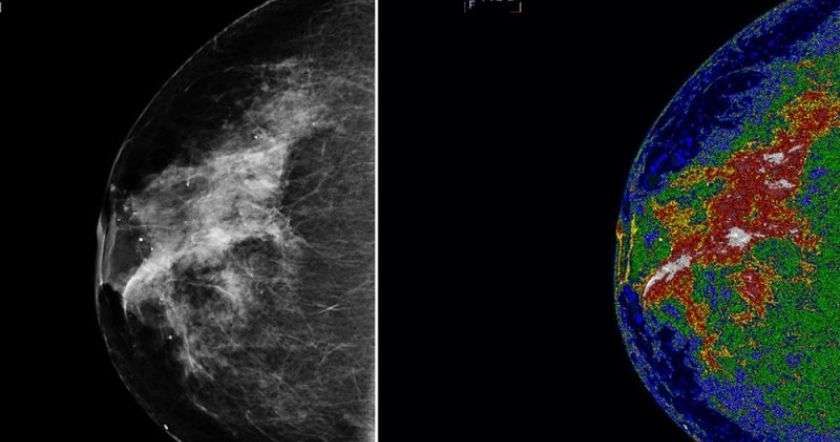

Анализ более полумиллиона женщин в Швеции показывает, что маммографический скрининг снижает частоту распространенных и смертельных случаев рака молочной железы.

Для анализа Ласло Табар, доктор медицинских наук из Центральной больницы Фалуни, Швеция, Стивен Даффи, магистр Лондонского университета королевы Марии, и их коллеги изучили данные почти трети женского населения в Швеции. Среди более чем 549 тыс. женщин исследователи рассчитали частоту прогрессирующих раковых заболеваний молочной железы и случаев, закончившихся смертельным исходом в течение 10 лет после постановки диагноза. Для сравнения использовались результаты женщин, которые участвовали в рекомендованном маммографическом скрининге, и тех, кто этого не сделал.

Команда обнаружила, что у женщин, проходящих профилактические проверки, количество случаев рака, закончившихся смертью в течение 10 лет, было ниже на 41%. А частота прогрессирующего рака была ниже на 25%.

«Это исследование показывает, что участие в скрининге рака молочной железы существенно снижает риск заболевания со смертельным исходом», - отмечает доктор Даффи.